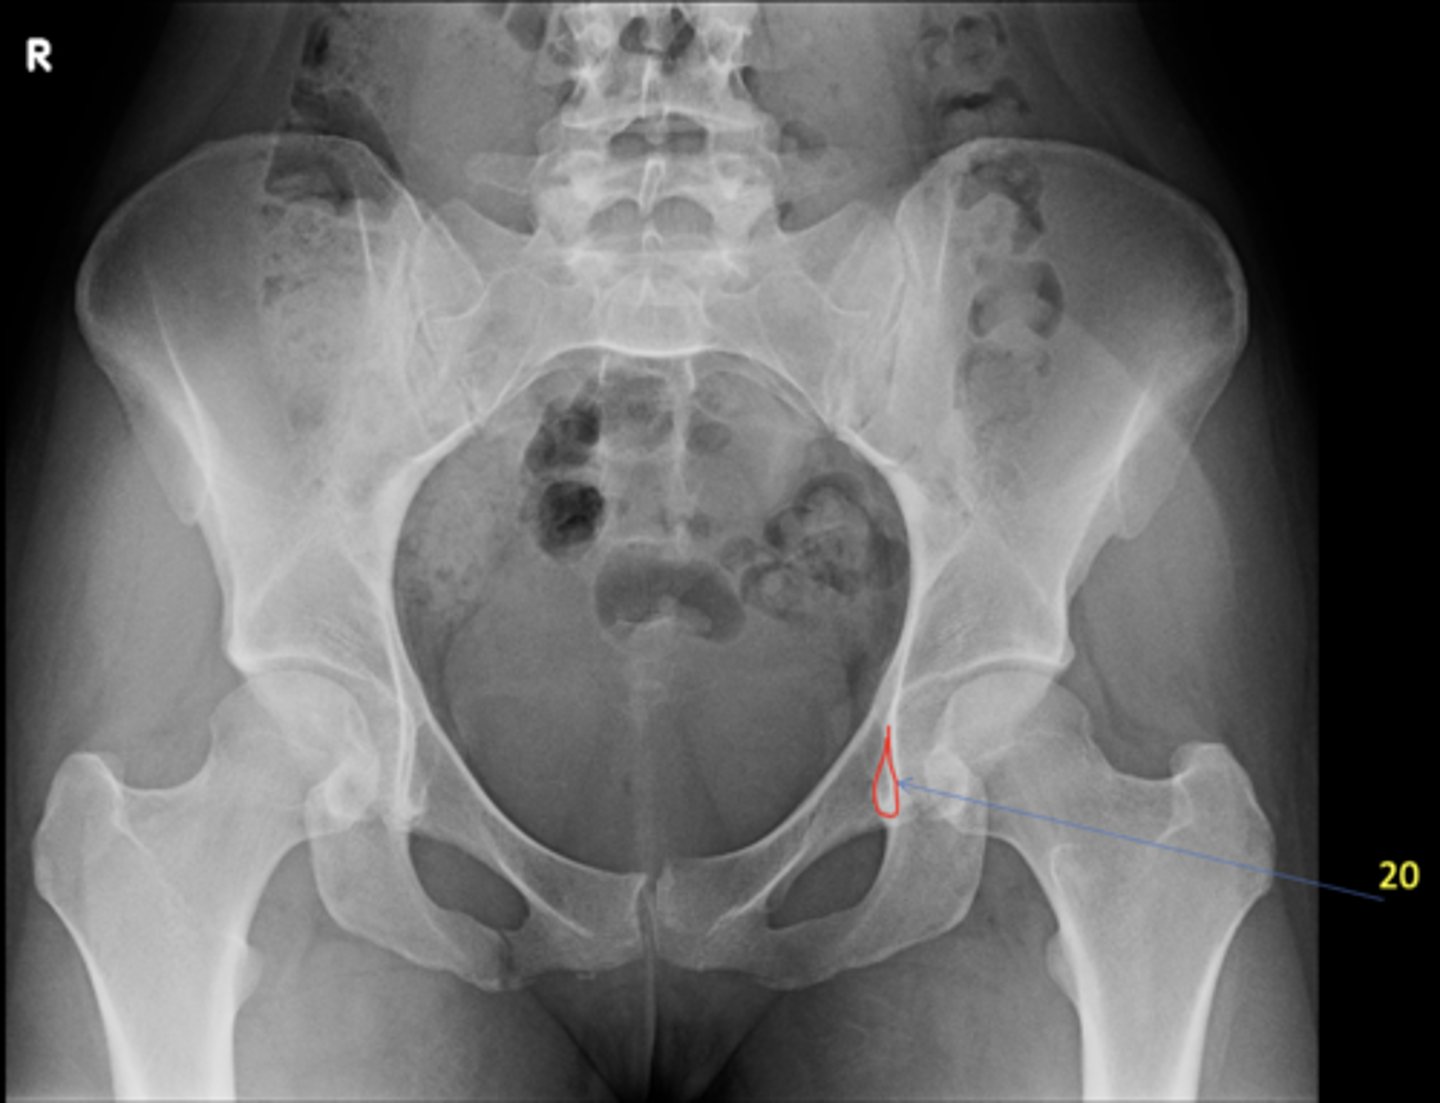

1

New cards

AP pelvis

View?

<p>View?</p>

18

Kohler's teardrop

ID 20

<p>ID 20</p>

20

Right anterior sacroiliac joint

ID 22 (joint)

<p>ID 22 (joint)</p>